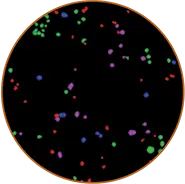

Vybrant#7キットで得られた蛍光画像(図1)

図 1 に示すように、最大濃度のスタウロスポリンの存在下では、3 種類の染料で非常に明瞭な染色パターンが得られました(図 1 の上部のシングルチャンネル画像、または下部の重ね合わせ画像)のに対し、未処理細胞では YO-PRO1 と PI 染色はほとんど認められませんでした(下部の DMSO ビヒクル処理細胞の重ね合わせ画像)。これは、アポトーシス過程のさまざまな段階に対する染料の特異性と、染料からのシグナルを分離するイメージングシステムの能力を示しています。